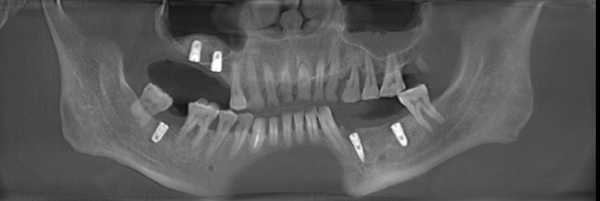

种牙前以为手术过程中会感觉到疼痛,结果轻松就完成了,并且手术后也没有什么不良反应,感觉非常好。麦芽种植专家根据CT拍片的牙槽骨数据和口腔健康情况分析,采用了微创无痛种植方案。这种手术最大的优点是只有3-4毫米微小切口,减少了肿痛和出血量,手术时间短,种植位置更准确,成功率也更高。